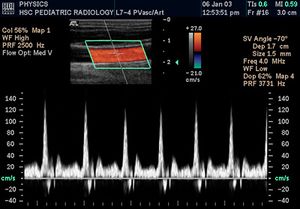

التخطيط الصدى الدوپلري

تكون الصورة عادةً ملونة، فيظهر الدم اما بلون أحمر أوأزرق حسب اتجاه الجريان بالنسبة للمجس الفاحص. ويقدم الجهاز معلومات ممتازة في تقييم صمامات القلب وارتفاع الضغوط الدموية في الأوعية الدموية.